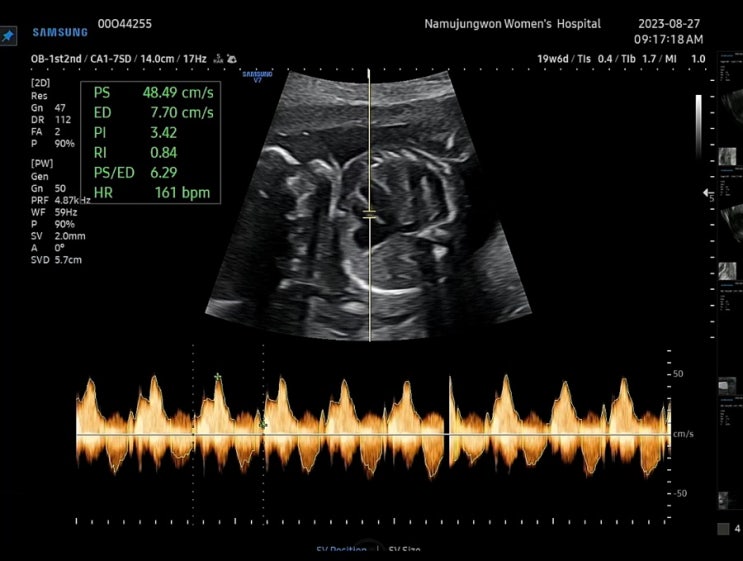

임신 19주 6일 정기검진 우동이 성별 확정!

임신 19주 6일차. 분만병원의 정기검진 날이에요. 둘째라 그런지 시간이 왜 이렇게 빨리 가는건지 ㄷㄷ 자...

동탄제일병원 자궁경부무력증 예방맥수술 후 첫진료 / 우동이 성별

첫째때 자궁경부무력증으로 24주때 양막 돌출, 응급맥 수술을 했지만 다행히 38주에 정상 분만하긴 했어요!...